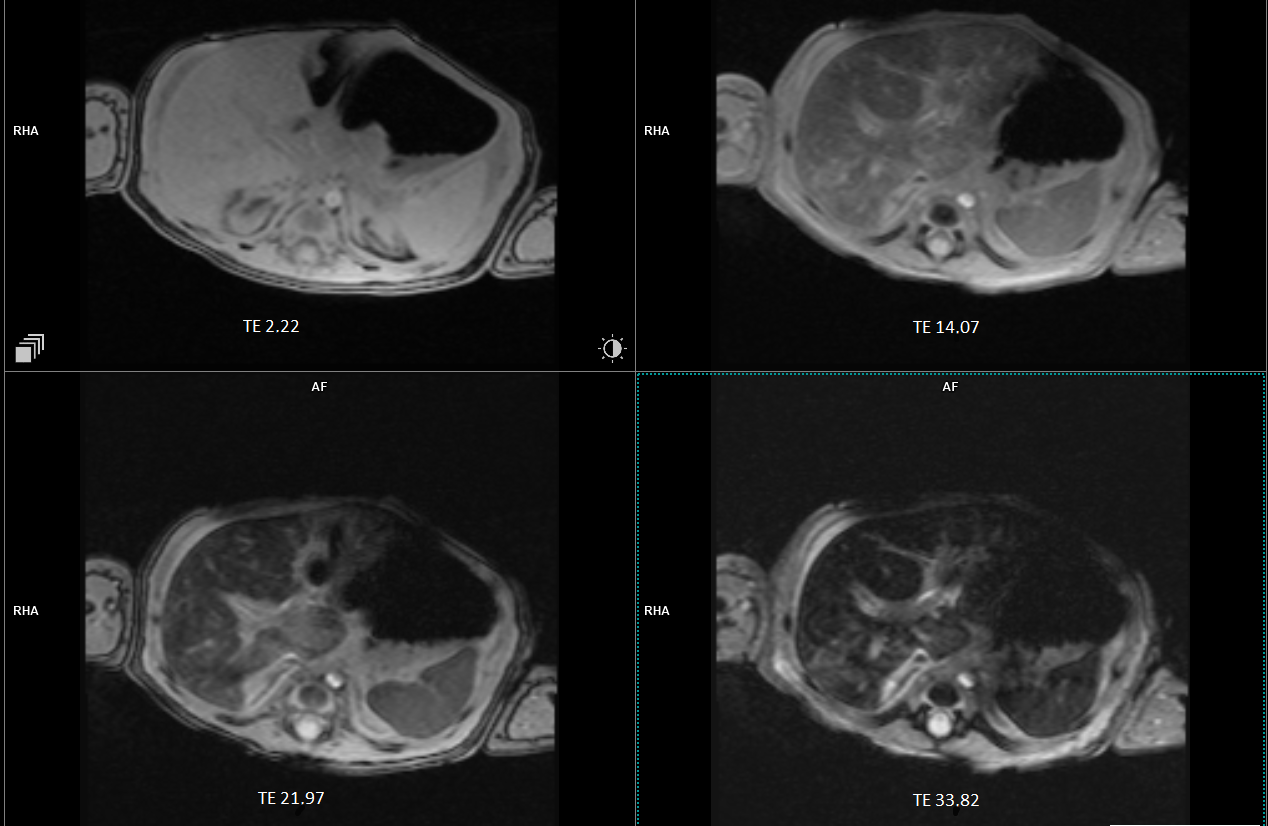

Hemophagocytic lymphohistiocytosis (HLH), gestational alloimmune liver disease (GALD), congenital metabolic disorders, and viral infections, such as CMV, EBV, HSV, and HHV-6, are some of the differential diagnoses that were taken into consideration. The patient was serologically negative for cytomegalovirus, Epstein–Barr virus, herpes simplex virus-1 and -2, human betaherpesvirus 7, varicella zoster virus, adenovirus, enterovirus, parechovirus, and parvovirus B19. The findings were inconclusive for human herpesvirus 6, while positive fungal infection biomarkers were noted; however, the lack of clinical fungal infection signs, sterile cultures, and clinical improvement without antifungals suggested it was most likely a false positive due to contamination. Abdominal magnetic resonance imaging (MRI) revealed decreased signal intensity in the liver parenchyma, with T2-weighted imaging showing no pancreatic abnormalities, suggesting only hepatic siderosis (Figure 1). The thyroid gland MRI was normal, while the brain MRI revealed several 5 mm ring-shaped calcified lesions. Screening for congenital metabolic disorders, such as plasma amino acids, gas chromatography–mass spectrometry (GC-MS), acylcarnitine profile, transferrin isoforms, creatine kinase, and ammonia, was unremarkable, and infectious diseases revealed nondiagnostic findings, ruling out these conditions as primary etiologies of acute liver failure. Furthermore, lactate levels that showed normal values and lack of hallmark radiological findings led to the conclusion that it was unlikely to be of metabolic etiology. The positive response of our patient to receiving IVIG further supported the likelihood of an immunological cause of the disease, resulting in GALD being the most probable diagnosis. Tyrosinemia Type 1 was excluded based on negative succinylacetone test results. Anti-fetal hepatocyte IgG testing was not performed in this case. The collective decision not to conduct liver, salivary gland, and lip biopsies was made by the team of doctors as the patient was in a critical state characterized by severe coagulopathy (prolonged PT and aPTT, markedly reduced fibrinogen, and elevated D-dimer), severe anemia, hemodynamic instability, and respiratory failure. The risks of performing the biopsies, including severe bleeding, anesthesia-related respiratory depression, hypotension, and potential exacerbation of the patient’s respiratory failure, clearly outweighed the potential diagnostic benefits.

Diagnosis of NH relies on assessing iron levels, abdominal MRI, and biopsies. Abdominal MRI is a key diagnostic tool for NH, as it detects excessive accumulation of iron in the hepatic and extrahepatic tissues. However, some case reports [4,5] have suggested that NH diagnosis is possible even without demonstrating extrahepatic siderosis. Our patient may have experienced a milder form of NH, demonstrating a phenotype of the disease that presented with the absence of extrahepatic siderosis, which differs from the classic presentation of NH. Nevertheless, this feature supports the diagnosis of NH, even in cases where other diagnostic findings are inadequate. Liver biopsy with immunostaining for anti-human C5b-9 complex can also help to diagnose GALD-related NH, but tissue autolysis in stillborn fetuses may reduce the efficacy and accuracy of C5b-9 testing in these cases. Despite this, C5b-9 testing enhances specificity and prevents misdiagnosis, enabling early diagnosis and precise treatment [6]. However, MRI is the preferred primary diagnostic tool as it is less invasive [6,7]. Nonetheless, MRI has certain limitations, including potential false negatives in early or mild siderosis, which may lead to delays in diagnosis.

Figure 1. Abdominal MRI showing the decreased signal intensity in the liver parenchyma with no extrahepatic siderosis. MRI: magnetic resonance imaging.